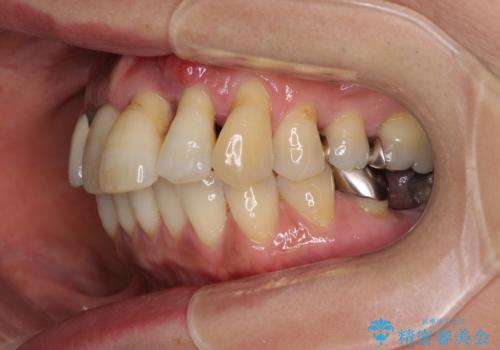

- 前歯の歯肉の腫れを気にして来院された患者様です。

前歯のみならず、奥歯の銀歯や下顎前歯のデコボコなど、色々と気になる部分を治したいとのことでした。

前歯は抜歯が必要であったので、抜歯を行い、その後歯肉移植をおこなった上でオールセラミックブリッジによる補綴治療を行うこととしました。

下顎と上顎臼歯部については矯正治療を行い、奥歯の欠損部位はオールセラミックブリッジを、その他の銀歯はセラミックインレーなどにより治療を行うこととしました。